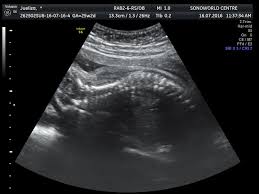

Ini antara sebab kenapa detail scan untuk bayi lebih penting dari scan 3d4d5d. Jika diikutkan pandangan pakar perubatan, sebenarnya tiada perbezaan signifikan yang akan dirasakan oleh wanita mengandung sama ada semasa mengandungkan anak lelaki ataupun perempuan. Dalam erti kata lain, anda mampu mengetahui jantina seawal usia janin pada umur 6 minggu kandungan. Bila dia tak boleh control mula la dia akan express emosi dia tu dengan macam macam cara. Kesimpulannya, entahlah nak pakai pendapat yang mana. • cadangan scan 4d dilakukan. Selalunya ini dinamakan skan anomali fetus dan digunakan juga untuk memeriksa posisi plasenta dan posisi bayi. Malah, anda tidak akan dapat menjelaskannya melalui perkataan, ianya merupakan satu perasaan yang membuatkan anda begitu bahagia.

Scan Bayi 2d 3d 4d Yang Mana Lebih Baik Untuk Ibu Hamil

Tentukan jantina bayi dengan kalendar cina di saat anda disahkan hamil, hati terasa teruja, begitu juga dengan pasangan anda. Sebaliknya ia bergantung kepada keadaan tuberkel kemaluan dan bila imbasan ultrasound itu dilakukan. Gambar scan bayi dalam kandungan ultrasound baby 6 bulan. For more information and source,. • cadangan scan 4d dilakukan. Tapi kali ni takdek sangat. Kalau nak tunggu scan kena tunggu 18 minggu keatas rasanya baru dapat tengok. Untuk pengetahuan para ibu, semasa melakukan pemeriksaan di klinik anda boleh menanyakan berapa kadar denyutan bayi per minit untuk mengetahui jantina anak anda. Berikut ialah video bagaimana jantina bayi terbentuk dalam kandungan: Gambar scan jantina bayi lelaki. • scan 3d adalah kaedah mencerap imej janin pada 3 dimensi. Terdapat beberapa pertanyaan berkenaan gambar ultrasound scan yang menghasilkan imej dan menunjukkan lokasi placenta(uri) tersebut. Ini antara sebab kenapa detail scan untuk bayi lebih penting dari scan 3d4d5d.

Bila dia tak boleh control mula la dia akan express emosi dia tu dengan macam macam cara. Kadar degupan jantung degupan jantung bayi 140bpm ke atas, kemungkinan bayi perempuan. For more information and source,. Apabila sebut sahaja keterujaan menjadi 'first time parents', sudah pasti aspek keselamatan, pemakanan sehingga ke soal persiapan perlu diambil kira. Pada usia kehamilan 20 minggu, perbezaan antara lelaki dan perempuan menjadi lebih jelas dan lebih mudah dikesan kerana cecair ketuban yang banyak. Dalam erti kata lain, anda mampu mengetahui jantina seawal usia janin pada umur 6 minggu kandungan. Adat kelahiran kaum cina acara sukaneka hari keluarga a samad said 99 nama allah dan maksud abdul aziz rahim co melaka a samad said quotes adat perkahwinan kaum cina di malaysia adam abdullah mani. Malah, anda tidak akan dapat menjelaskannya melalui perkataan, ianya merupakan satu perasaan yang membuatkan anda begitu bahagia.